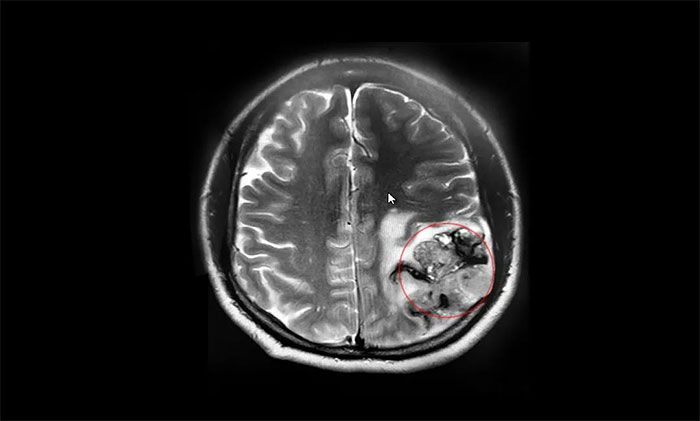

▲ MRI顯示腫瘤最大直徑超7厘米大小

因著這一線生機(jī),張先生再次帶著妻子來到上海,轉(zhuǎn)入上海藍(lán)十字腦科醫(yī)院。入院檢查時(shí),頭顱MRI平掃+增強(qiáng)提示:左側(cè)額頂葉占位性病變,最大徑約4.2×7.4×4.3cm,如鵝蛋般大小。

對(duì)照患者病史和影像學(xué)檢查報(bào)告,李士其教授、黎軍主任、潘仁龍主任會(huì)診后一致認(rèn)為膠質(zhì)瘤可能性大,且已嚴(yán)重威脅患者生命,應(yīng)盡快進(jìn)行手術(shù)治療,明確病理診斷。